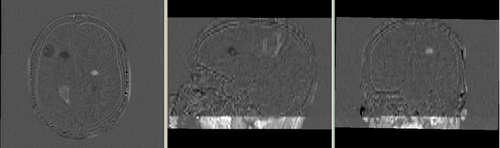

before registration: Orig. MRML Data tree after registration: Registered. MRML Data tree: exam 2 is within nested affine transforms